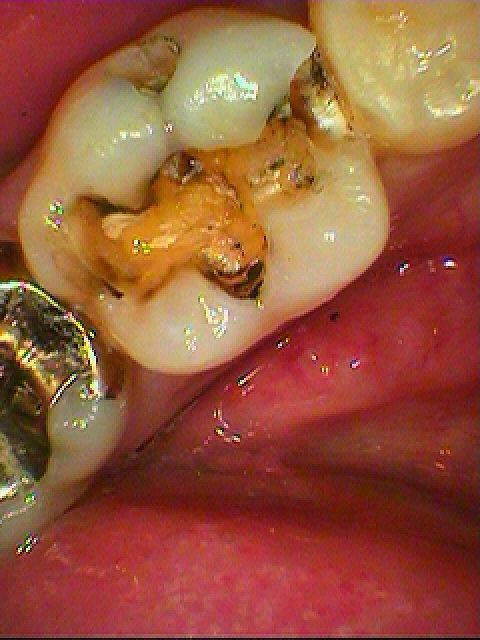

アマルガムの水銀が良くないためと適合が悪くなったことによるやり変え|お知らせ |広島市安佐南区の歯科医院 アマルガムの水銀が良くないためと適合が悪くなったことによるやり変え トップ お知らせ・ブログ お知らせ アマルガムの水銀が良くないためと適合が悪くなったことによるやり変え アマルガムの水銀が良くないためと適合が悪くなったことによるやり変え 近心隣接部に虫歯ができてきています 全体がなんだか黒い感じがします 頬側にも虫歯が、、、、 銀歯をはずし隣接部の虫歯も除去していきます このようにまた下で虫歯が広がらないように除去していきました セレックセラミックにて修復していきました Web診療予約 初めての方へ 選ばれ続ける理由 院内設備について 歯が痛いしみる一般歯科 歯がぐらぐらする歯周病 健康な歯を保ちたい予防歯科 子供の虫歯予防をしたい小児歯科 銀歯をセラミックに審美歯科 白い歯を目指しませんか?ホワイトニング 矯正専門医がいるので安心矯正歯科 抜けた歯を補いたいインプラント・入れ歯 医院案内 スタッフ紹介 メリィハウス歯科クリニックオフィシャルホームページ ラベンダー歯科クリニックオフィシャルホームページ お知らせ・ブログ ホーム 診療科目 一般歯科 歯周病治療 予防治療 小児歯科 審美治療 ホワイトニング 矯正歯科 入れ歯・インプラント マウスピース矯正 初めての方へ 院長・スタッフ 設備紹介 医院案内・アクセス メニューを閉じる